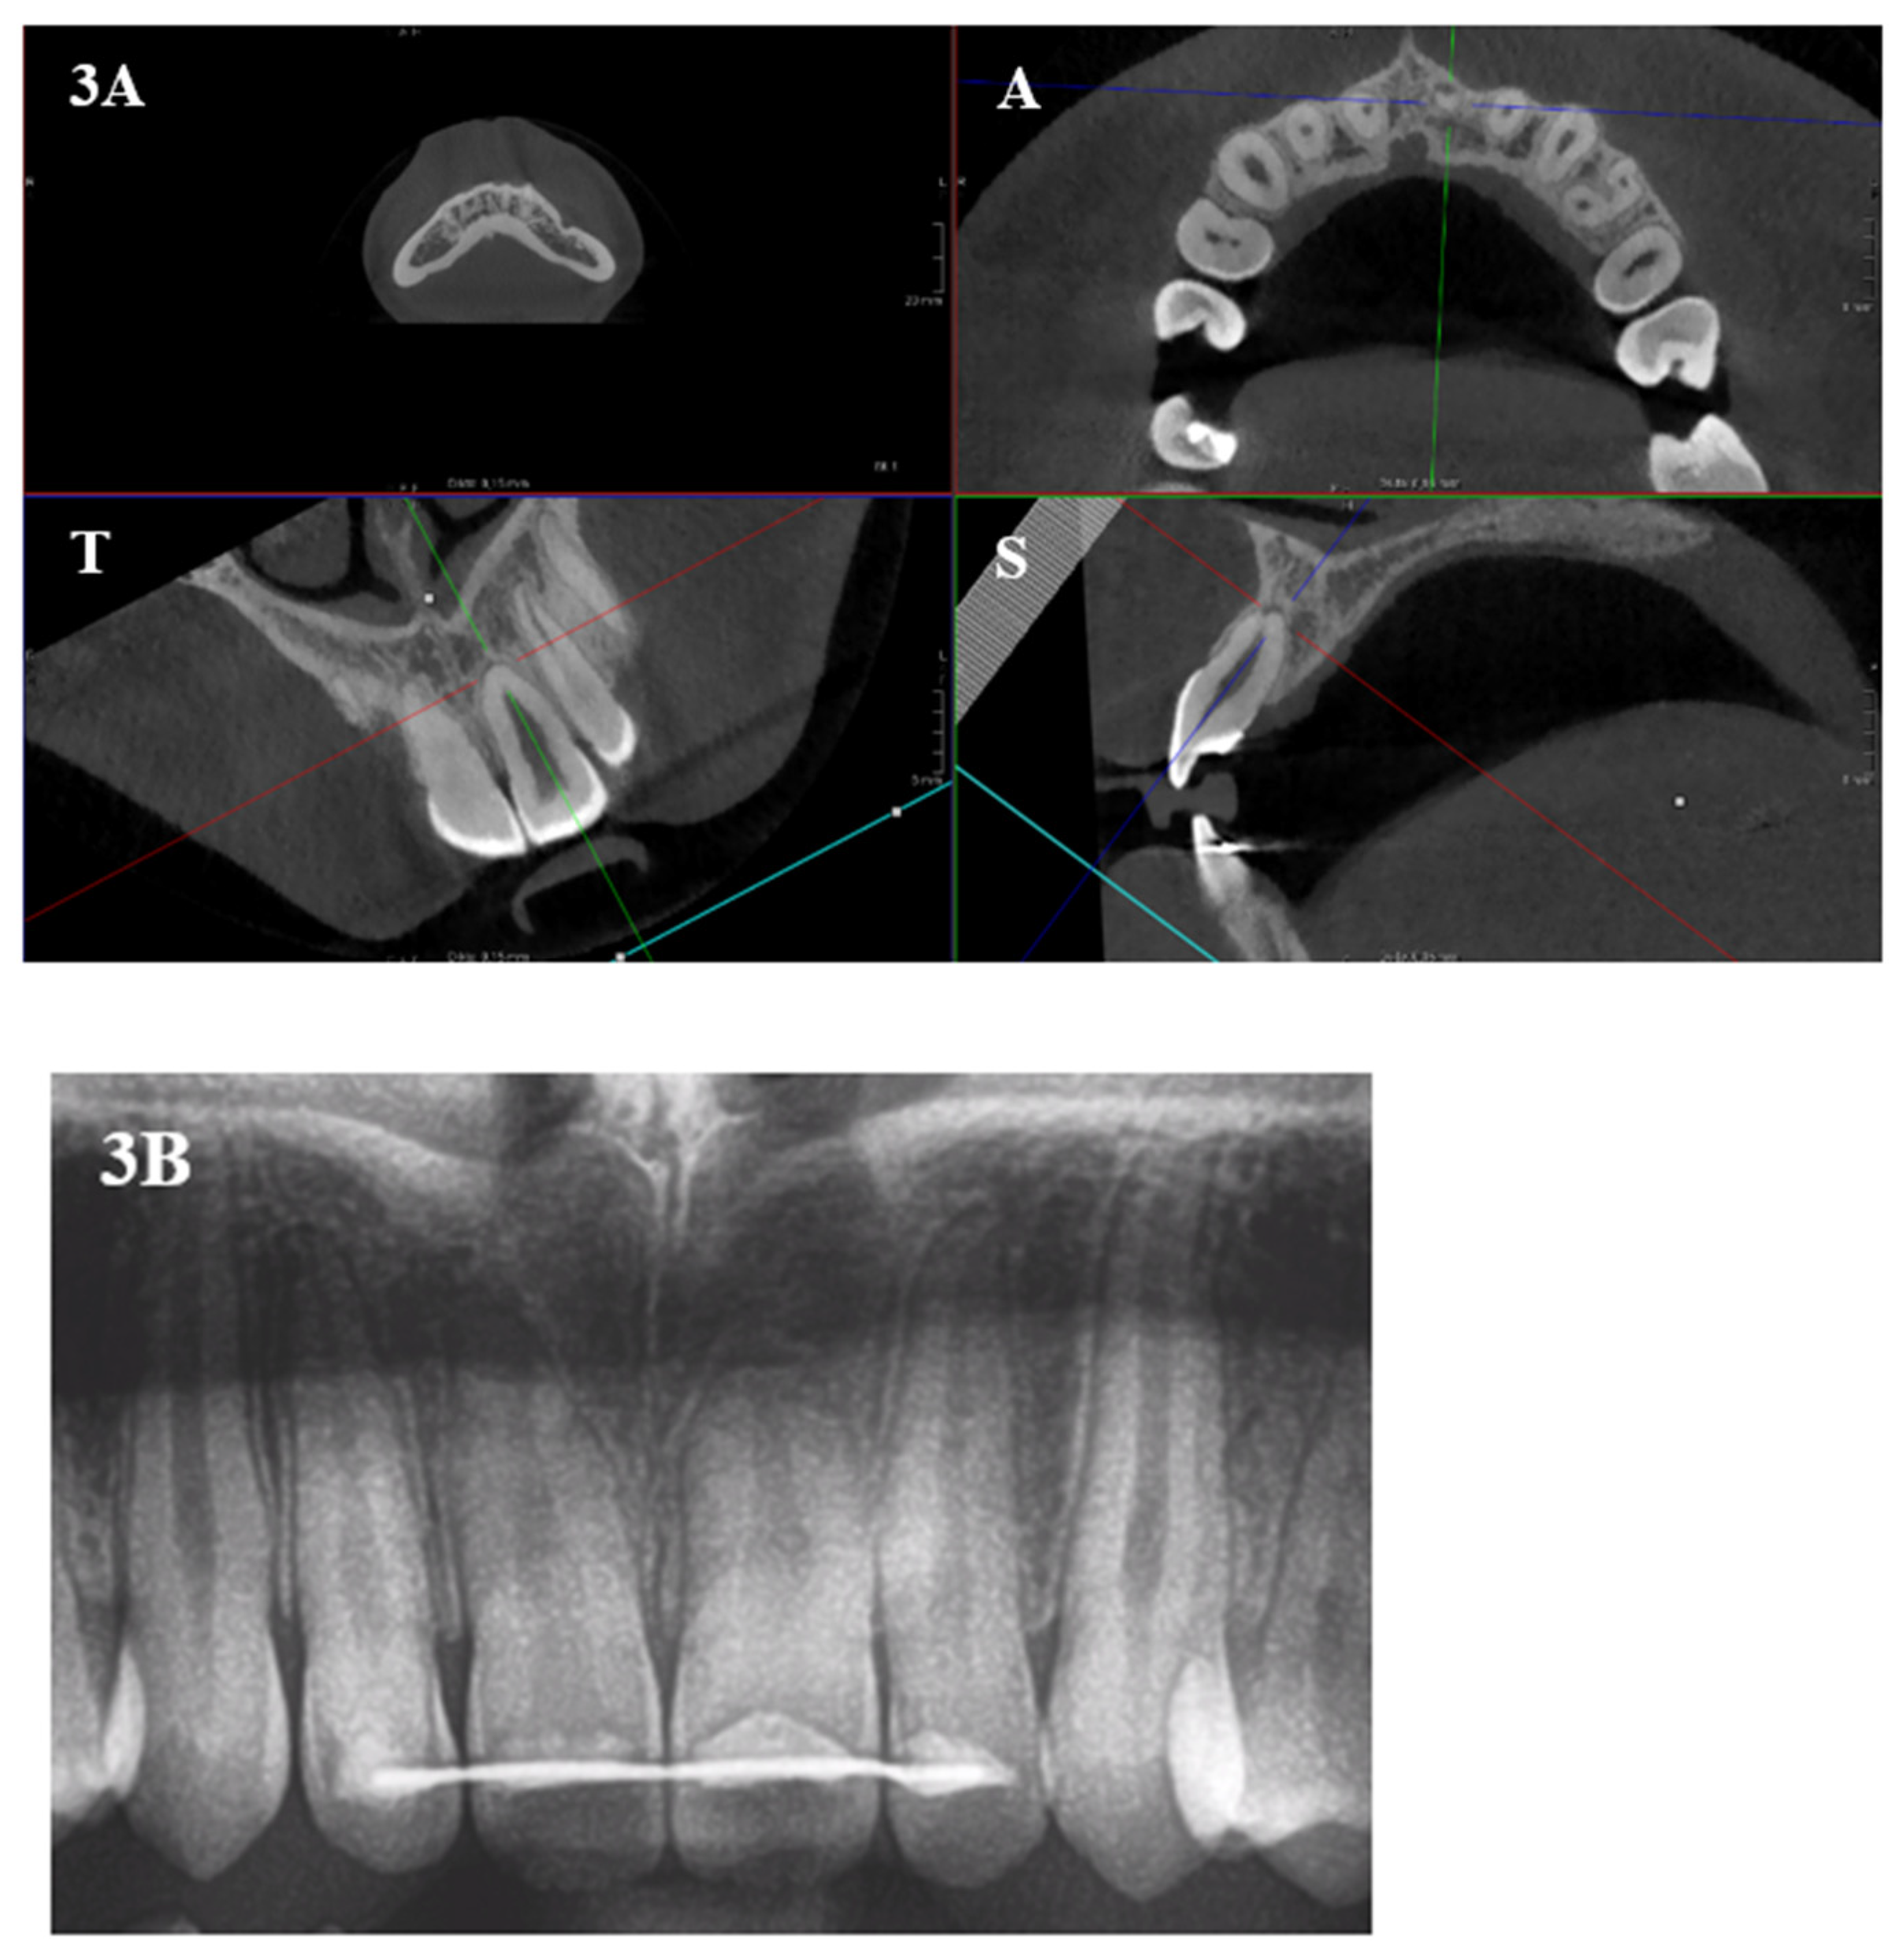

2. Materials and Methods

2.2. Methods